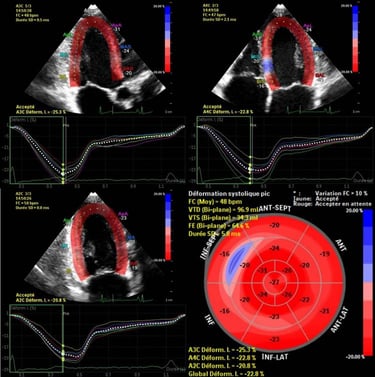

Échographie cardiaque

Évaluation de la structure, des valves et de la fonction du cœur en temps réel.